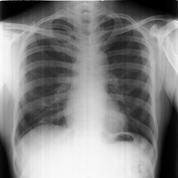

On investigation, an orthopantomogram (OPG) was advised. The radiograph reveals significant asymmetry of the mandible, with notable hypoplasia of the left condyle and a marked reduction in the vertical height of the left ramus. The left antegoinial notch appears prominently accentuated, suggesting altered mandibular growth. Despite these morphological changes, the cortical bone appears well-defined, with normal bone density and an intact lower border of the mandible. The glenoid fossa on the left side maintains a normal appearance, without evidence of dysplasia or displacement. In contrast, the right side of the mandible appears structurally normal (Figure 4).

Figure 4 Orthopantomogram showing mandibular asymmetry with hypoplastic left condyle, reduced vertical height of the left ramus, and a prominent antegonial notch. Cortical bone and mandibular border are intact with normal bone density. The left glenoid fossa appears normal; the right mandible is structurally unremarkable.

Radiographic imaging further supports the diagnosis. The orthopantomogram (OPG) reveals mandibular asymmetry, left-sided condylar hypoplasia, and a reduction in vertical ramus height, all of which are indicative of the mandibular underdevelopment typical of Nager syndrome.10 The prominent antegonial notch also points to abnormal mandibular growth, a finding frequently reported in these patients.17 Despite these skeletal changes, the well-defined cortical bone suggests that severe osteodysplastic conditions are unlikely.